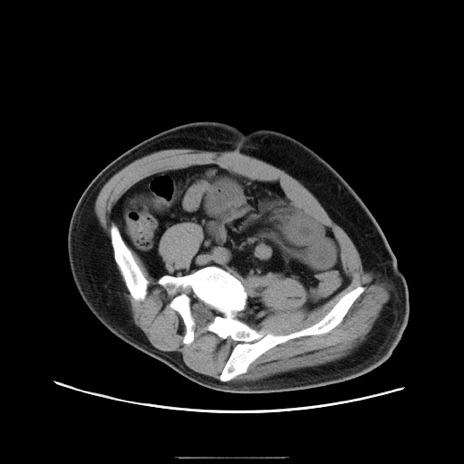

症例22(横断像)

【症例】50歳代男性

【主訴】腹痛

【現病歴】AVMからの被殻出血のため回復期リハ病棟入院中。 本日午後3時頃急に下腹部痛が出現した。

【既往歴】AVM、被殻出血、虫垂炎、高血圧

【身体所見】意識晴明、左半身不全麻痺、会話の理解は良好、36.5°C、腹部:膨隆、全体に板状硬、下腹部正中に圧痛点あり、反跳痛-、筋性防御不明、右下腹部にope scar

【データ】WBC 9400、CRP 0.06